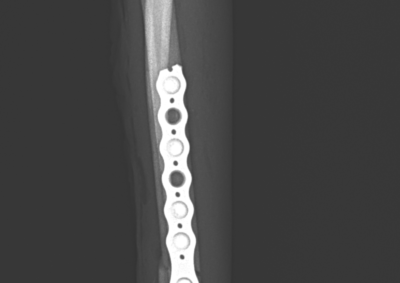

整形外科 注意 ボタンをクリックした先に、治療中および手術中の画像が説明で使用されている場合がございます。 そのような画像に弱い方は閲覧なさらないようお願いいたします。 整形外科 上腕骨外顆骨折の癒合不全 整形外科 大腿骨遠位開放および粉砕骨折 整形外科 膝蓋骨内方脱臼+前十字靭帯断裂 PGR#21+CBLO #251 整形外科 犬の前十字靭帯断裂に対するCBLO #250 整形外科 脛骨粉砕骨折 整形外科 内側鉤状突起分離症(Fragmented Medial Coronoid Process:F... 整形外科 股関節全置換術(トータル・ヒップ・リプレイスメント)#27 整形外科 橈骨固定術 #268 整形外科 橈骨固定術 #267 整形外科 橈骨固定術 #266 整形外科 股関節脱臼に対するBUSTOR #67 整形外科 脛骨粗面剥離骨折 <1234567> 症例カテゴリー 放射線治療整形外科軟部組織外科脳神経外科内科腫瘍外科救急・集中治療リハビリテーション科腫瘍内科内視鏡科脳神経科呼吸器外科中医・漢方猫の腎移植循環器科